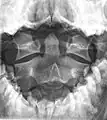

Axis on X-ray taken through an open mouth, teeth visible